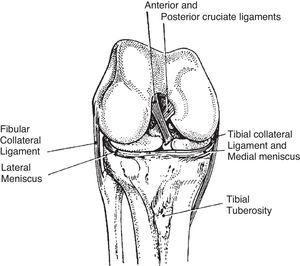

This simple diagram shows 2 most important attachment sites. One is “for iliotibial tract”. This site is unnamed in the Terminologia Anatomica but is widely known by clinicians as lateral tubercle of tibia or Gerdy's tubercle. The other site is the tibial tuberosity where the patellar tendon attaches.

Sketch of a transverse section of the knee. The medial meniscus is like a C and the lateral meniscus almost like an o. The fibular collateral ligament is extracapsular. The tibial or medial collateral ligament is capsular. The cruciate ligaments and the initial portion of popliteus tendon are intracapsular but extrasynovial.